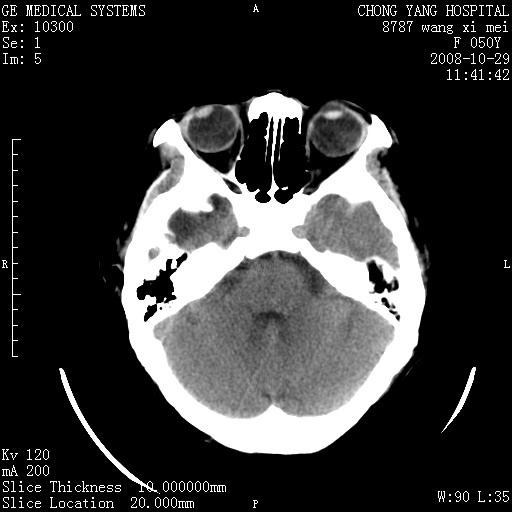

标题: CT16469:女,50岁,胶质瘤术后6年,今平扫加增强,请大家帮 [打印本页]

标题: CT16469:女,50岁,胶质瘤术后6年,今平扫加增强,请大家帮

右侧颞顶部可见低密度实变影,内见不规则钙化灶,边界不清,占位效应明显,侧脑室后角受压移位,符合胶质瘤术后复发改变。

右颞骨局限性缺如,局部脑组织无外隆。右颞叶可见片状脑脊液样低密度影,边缘较清,右侧侧脑室三角区可见一块状等密度影,且伴有强化,余未见明显异常改变。

考虑:右大脑术后改变伴肿瘤复发。